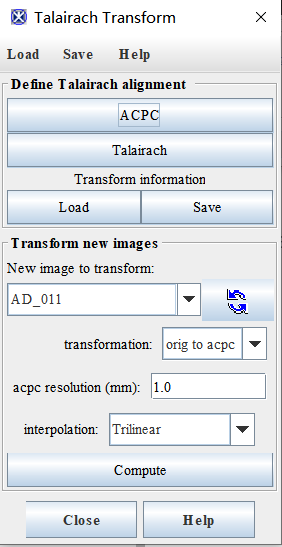

2、点击algorithm-brain tools-Talairash transformer

点击ACPC

(6)保存变换信息:最后点击Apply,会显示ACPC结果(和原图),可以点击save保存变换信息

然后点击load,将之前的变换信息加载进去就会显示ACPC变换后的图片,点击New image to transformer栏的刷新按钮,然后选择AD_011_ACPC

然后将transformation改成acpc to orig,点击compute可以将变换后得图片和原图进行对比(不晓得有啥用)